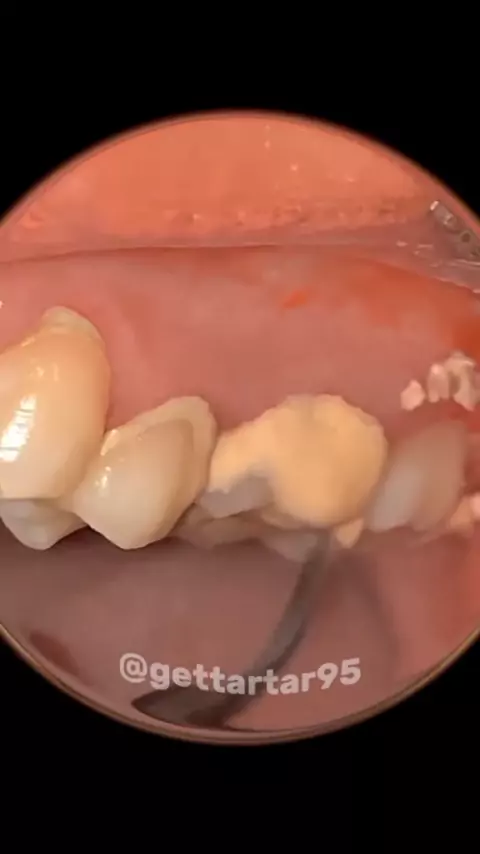

User_dentes bem restaurado

#dentes #viral #fy